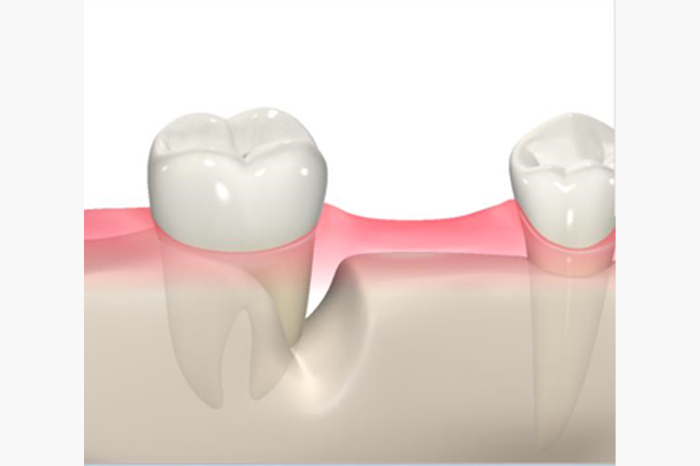

歯周病を放置すると・・・

歯周病を放置した場合の歯と歯ぐきの状態のイラスト

歯周病を放置してしまいますと、歯ぐきを切って歯ぐきのなかについた歯石を取らないといけなくなります。

治療の侵襲が大きくなりますし、治癒にも期間がかかりますので、放置は禁物です。

最悪の場合は抜歯となってしまいますので、放置していいことはないですね。